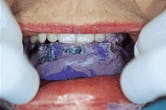

Figure 1-The patient has had four implants placed in the mandibular anterior segment. The denture is unsatisfactory to the patient in the three critical areas of esthetics, comfort and function.

Figure 1